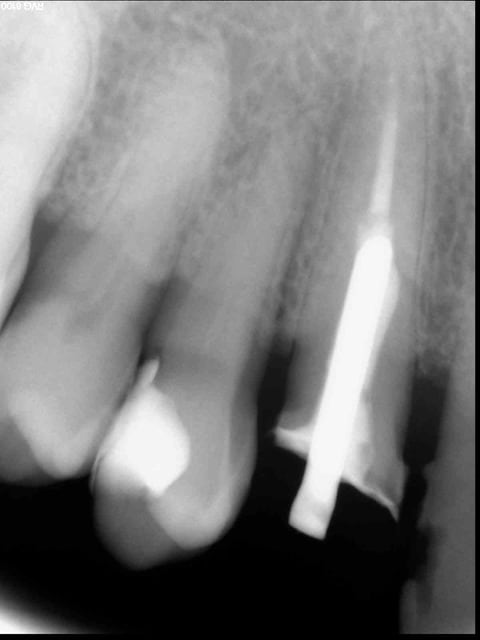

@youn , je bosse dans un cabinet "normal" dans une ville "normale" dans une région "normale", bien sur pas dans les beaux quartiers parisiens mais pas non plus dans les zup de banlieue ... sinon , une petite radio faite ce matin sur un nouveau patient de 70 ans ... la question est : de quand date cette "provisoire" ?

Moi même j'en suis restée sur le postérieur ...

La nature humain est bonne fille , enfin parfois même très bonne fille ....Alors il y a les données acquises de la science et puis il y a la nature humaine et là on est plus dans le vague ....

Quant à ta radio : on a tous déjà vu des cas "miraculeux", une endo avec un peu de pate à l'entrée des canaux sur une dent qui va très bien depuis 40 ans. C'est le jeu des statistiques, les lois de Gauss tout ça tout ça. Ca ne justifie en aucune manière de faire des endos de cette manière là. Prétendre le contraire est un déni de la science, pour des personnes de formation scientifique c'est pour le moins étrange... Les biostats n'ont pas été inventées pour rien, il serait pas mal que bon nombre de praticiens s'y mettent un peu (ne serait-ce que pour comprendre les articles qu'ils lisent (liraient est plus juste ici...))